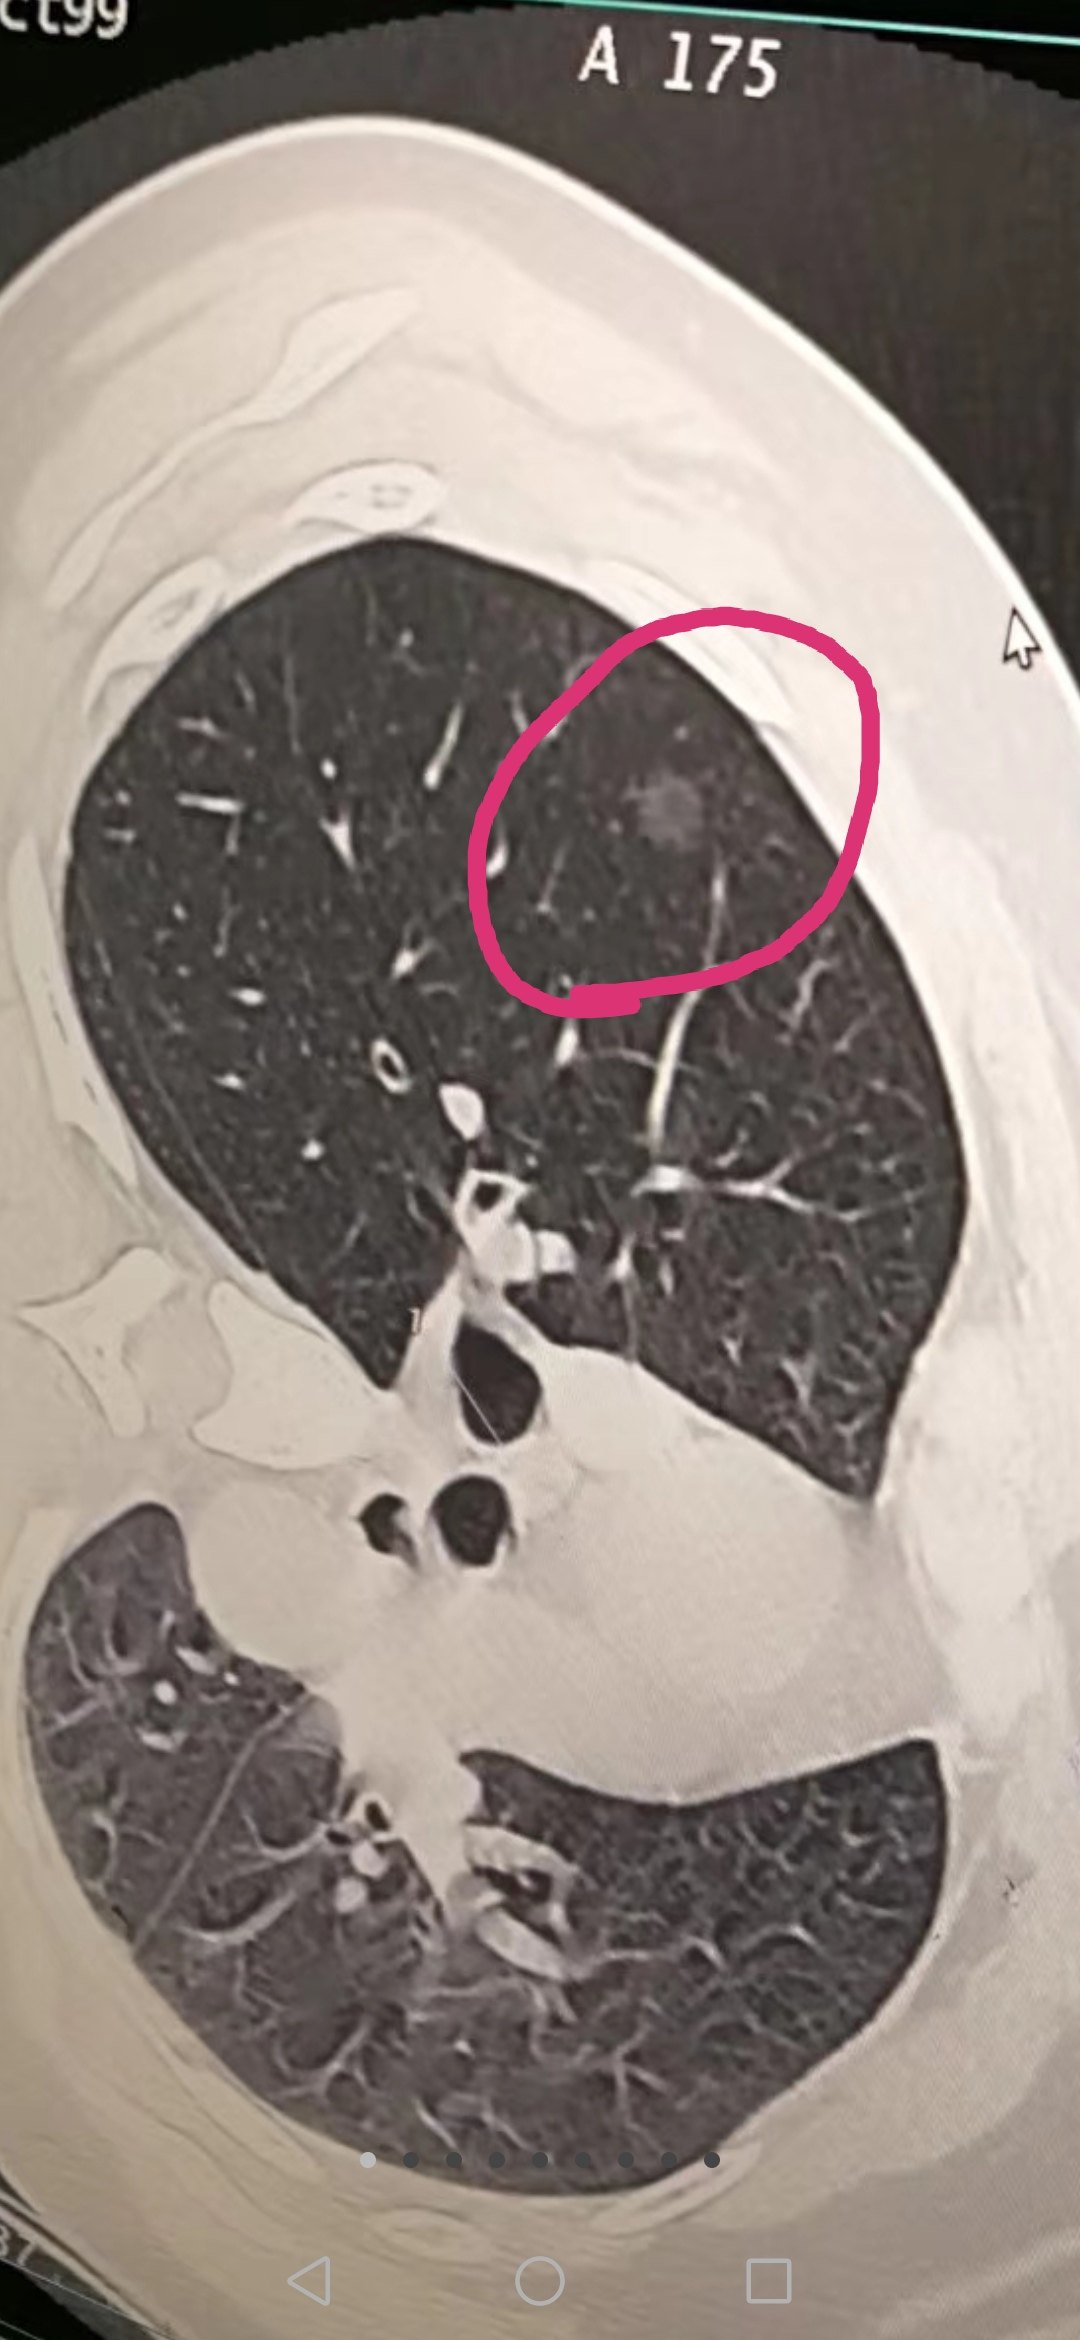

Screenshot_20200119_081214.jpg

只可惜,由于多种原因,比如:有的患者不体检筛查,有的医师不认识、不负责任,设备技术落后或运用不当等,绝大部分肺癌患者都不能在早期发现病灶,导致目前肺癌死亡率很高,而且当中的5年生存率达不到20%。这是因为大部分人在发现肺癌时就已处于中晚期,失去了手术的最佳时期。大家都知道,一旦失去了最佳手术时期,即使可以手术切除肿瘤,但术后出现转移的机会也会非常大,预后不好。